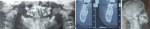

Diagnostic assessment: firstly, we requested a panoramic radiograph (Figure 3A). This examination provided an initial overview of the patient´s dental development, confirming the presence of unerupted permanent teeth, including premolars, second permanent molars, and wisdom teeth. Three additional tooth germs were also identified on the lower left side, and one on the lower right. A fourth and final supernumerary tooth was located lingual to the right lower second premolar (#45), as visualized using cone beam computed tomography (CBCT) (Figure 3B). To confirm the presence of disharmonious maxillo-mandibular development, a lateral cephalometric radiograph was prescribed. This revealed an abnormally radiolucent appearance of the cranial vault sutures, corroborating the clinical finding of open cranial sutures on palpation (Figure 3C).

Figure 3: radiographic examinations of the patient: A) panoramic radiograph; B) oblique cross-sectional images from cone beam computed tomography (CBCT) showing an additional unerupted tooth germ located lingually to the right mandibular second premolar (#45); C) lateral cephalometric radiograph